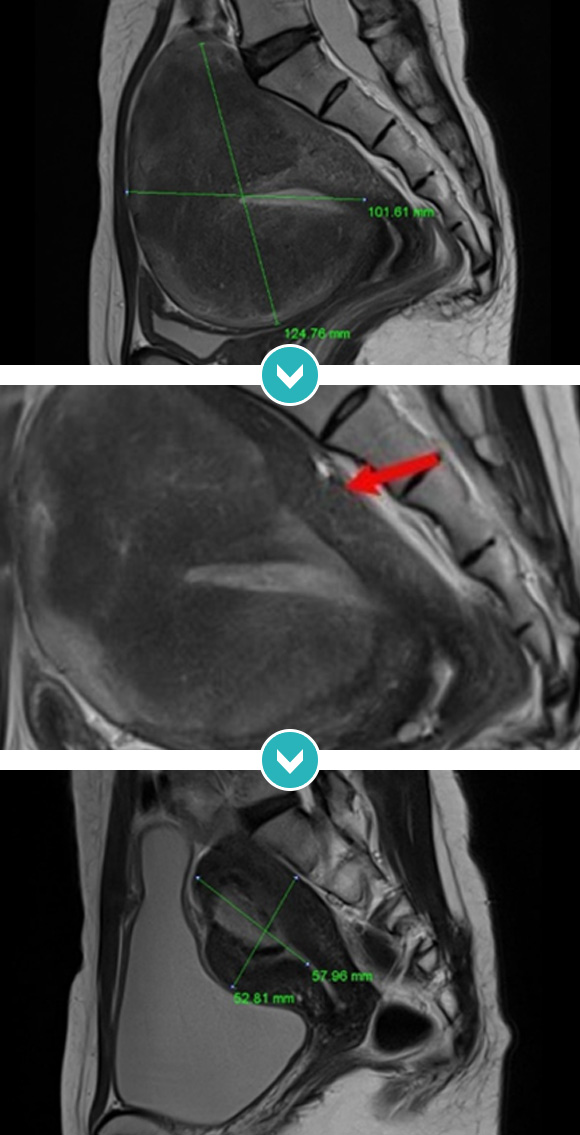

14cm 거대 자궁근종 하이푸 치료후 80~90%이상 치료, 6개월 추적관찰